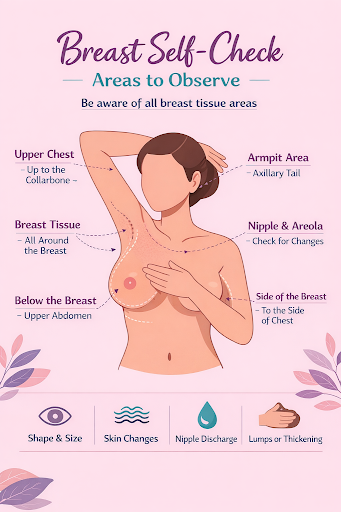

A simple way to stay aware of your body

Breast self-examination is a gentle, at-home practice that helps you become familiar with how your breasts normally look and feel. This awareness makes it easier to notice changes early and seek timely medical advice when needed.

A self-exam takes only a few minutes and involves looking at your breasts and feeling them with your fingers. Breast tissue extends beyond the breast mound — up to the armpits, collarbone, and upper abdomen — so the exam includes these areas as well.

A breast self-exam does not replace medical screening or doctor visits. It is a tool for awareness, not diagnosis.

Breast self-examination is a gentle, at-home practice that helps you become familiar with how your breasts normally look and feel. This awareness makes it easier to notice changes early and seek timely medical advice when needed.

A self-exam takes only a few minutes and involves looking at your breasts and feeling them with your fingers. Breast tissue extends beyond the breast mound — up to the armpits, collarbone, and upper abdomen — so the exam includes these areas as well.

A breast self-exam does not replace medical screening or doctor visits. It is a tool for awareness, not diagnosis.

How to Do a Breast Self-Exam +

1. Visual Examination (Looking)

2. Physical Examination (Feeling)

- Stand in front of a mirror with your shirt and bra removed

- Arms relaxed – observe size, shape, symmetry

- Raise arms – check again

- Hands on hips – tighten chest muscles and observe

2. Physical Examination (Feeling)

- Use finger pads with light → medium → firm pressure

- Move in circular pattern

- Cover entire breast and armpit

- Check nipple for discharge

What Needs Attention +

Contact a healthcare provider if you notice:

- A new lump or thickened area

- Skin changes or redness

- Nipple discharge

- Nipple inversion

- Persistent localized pain